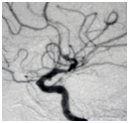

A 52 year-old man with previous Diabetes type 2 was admitted after a two-day headache, nausea and transitory impairment conscious. At his entrance remained alert, presented bilateral VI CN paresis (Figure 3), showed no motor weakness in extremities and shed 15pts on GCS. Brain CT scan demonstrated SAH Fisher III. CT angiography showed an anterior communicating artery (AComA) aneurysm (Figure 4), obliterated with surgical clipping (Figure 5). The result was significant clinic evolution without recovery from the VI CN paresis at discharge. The mRS shed 1 in the late follow up and fully recovers from the VI CN paresis on the third month.

Figure 4 CT angiography demonstrates an AComA aneurysm.